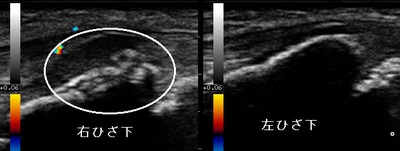

川越市 中学生 右膝関節の痛み オスグッド膝

川越市 男子中学生 サッカー部所属

右膝関節の痛み、オスグッドひざ。

右膝関節の痛み、オスグッドひざ。【原因】

雨の日に校舎内をランニング中

雨の日に校舎内をランニング中 、階段を駆け下りたときに右膝関節の下に激痛がはしり、その後運動を

、階段を駆け下りたときに右膝関節の下に激痛がはしり、その後運動を続けることができなくなりました。

【治療】

当日来院されて超音波検査の結果、右膝関節下部の脛骨粗面の軟骨が損傷している様子が認められました。

痛みが強かったのでアイシングしてから特殊な物理療法を行いました。

オスグッド膝になると損傷した軟骨が骨硬化するまでに数か月かかりますが、部活動と体育は運動強度を

制限制限しますが、1週間後の復帰を目指します。

膝を痛めてお悩みの方は、当院までお気軽にお問い合わせ下さいね